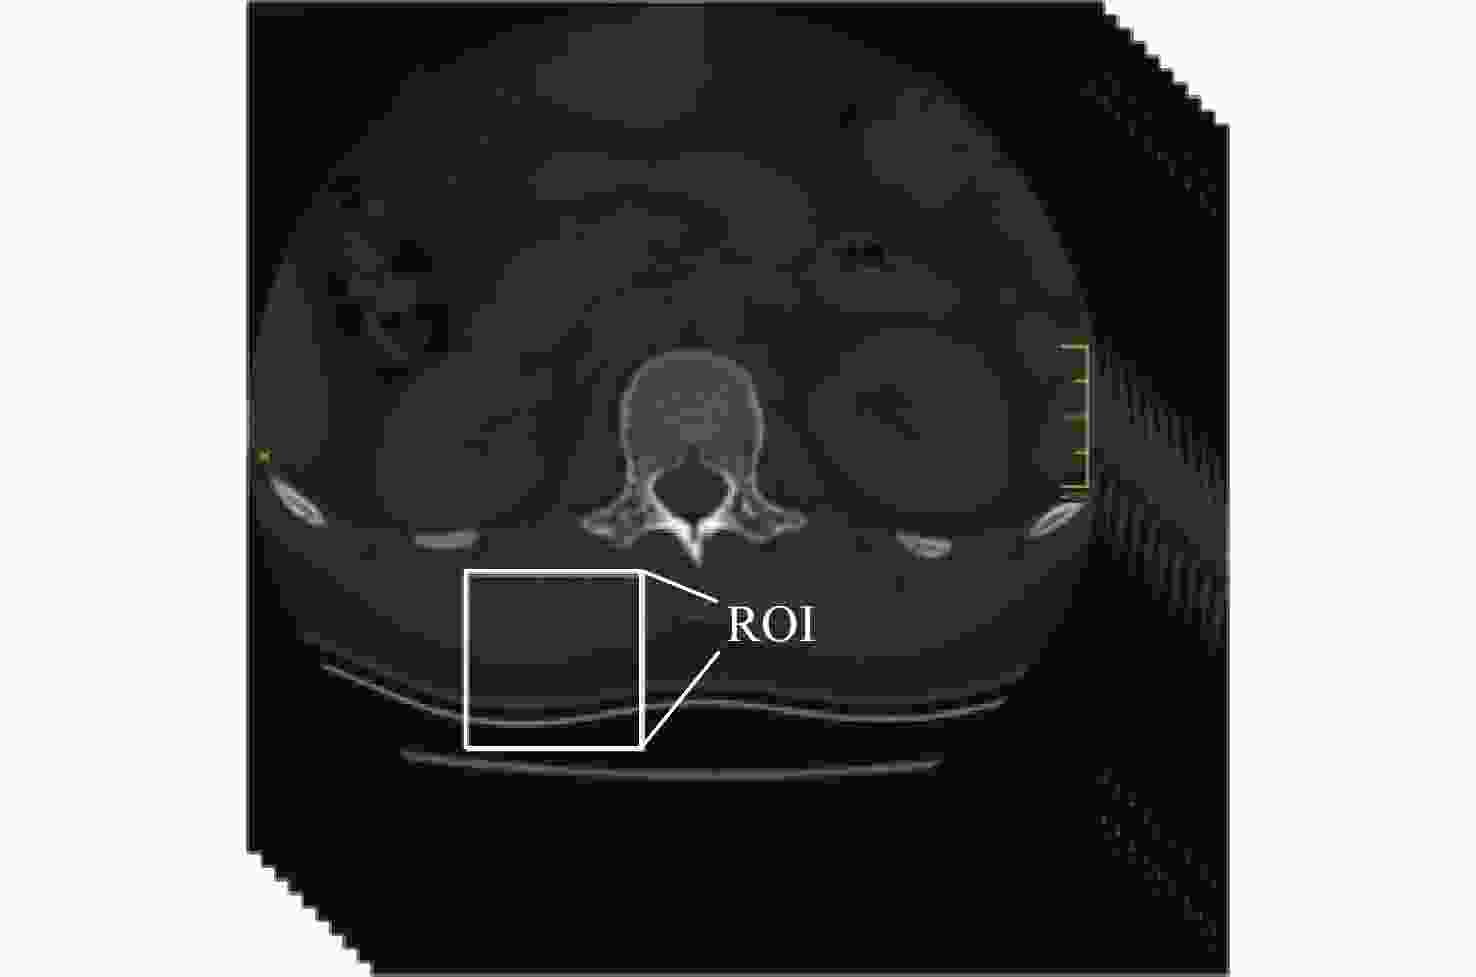

Abstract:In an attempt to accurately analyze high load, the finite element model established by clinical CT data was unable to capture the fine geometric features and heterogeneous properties of vertebrae, leading to an inaccurate analysis of the high rate of thoracolumbar spine injuries on fighter pilots during ejection. A finite element model of the thoracolumbar spine (T12-L2) was constructed based on nonlinear finite element, which represents the cortical thickness, cortical density, and cancellous bone density of specific-objects, to analyze the biomechanics of high load on the thoracolumbar spines of pilots during ejection. The object-specific finite element model was constructed based on the CT data of the thoracolumbar spine, and the cortical bone thickness and density values obtained from cortical bone mapping (CBM) were incorporated into the CT-based finite element modeling process of the thoracolumbar spine, and the elastic modulus of each element was calculated according to the Hounsfield units (HU) value to realize the heterogeneous assignment of material. By using the same loads and boundary conditions as those found in published in vitro studies, the model's correctness was confirmed. A Additionally, a simulation and computation were made of the biomechanical reaction of the thoracolumbar spine brought on by the ejection load in the upright, flexion, and extension physiological motion situations. The results showed that the vertebral load transfer characteristics were significantly different among the three different physiological motion conditions subjected to ejection loading, with the upright physiological motion conditions resulting in the least amount of direct acute injury to the vertebrae from the high load.